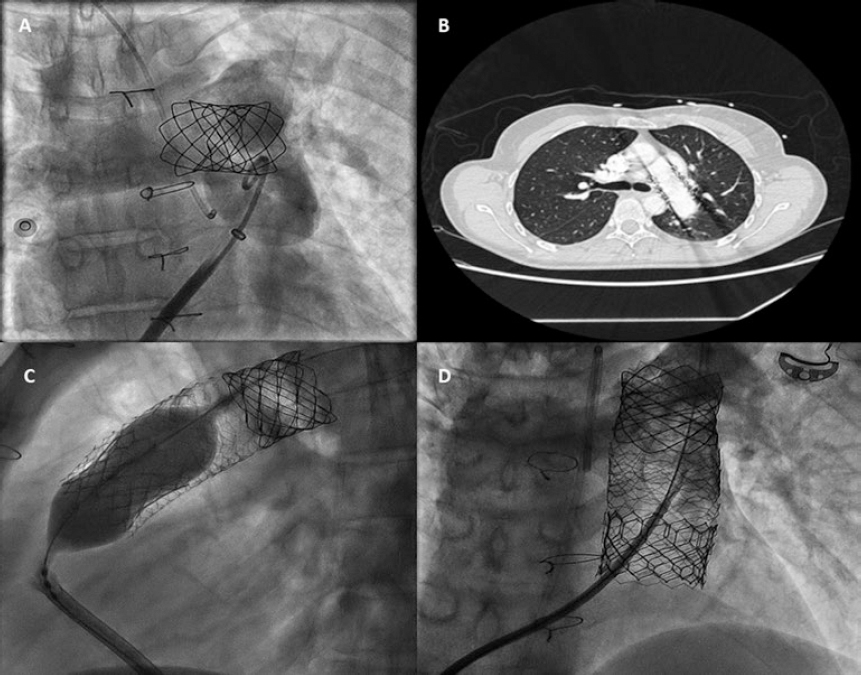

A 48-year-old woman with congenital pulmonary stenosis who required surgical valvuloplasty in 1978 presented with progressive dyspnea. The cardiovascular magnetic resonance imaging performed confirmed the presence of dilated right ventricle, severe regurgitation, and pulmonary artery aneurysm (39 × 25 mm). The heart team decided to perform a transcatheter pulmonary valve implantation. During pre-stenting with an uncovered 15-25 mm × 47-55 mm CP Stent (NuMED, United States) mounted on a 25 mm balloon of the native right ventricular outflow tract, stent embolization with spontaneous anchoring to the left pulmonary artery occurred (video 1 of the supplementary data, and figure 1A). Since the patient remained stable, a wait-and-see approach was decided to facilitate stent endothelialization. The stent (figure 1B) was used as the anchoring substrate 2 months apart of the proximal implantation for 2 longer Andrastent XXL 57 mm-stents (Andramed, Germany) on a 30 × 40 mm XL AndraBalloon to create a landing zone for the 29 mm Sapien-3 valve. The rest of the procedure was successful (figure 1C). The patient remained asymptomatic, with no perfusion defects as confirmed by the ventilation/perfusion lung scan and a mean transvalvular gradient of 7 mmHg without any residual regurgitation at the 6-month follow-up (figure 1D).

Figure 1.

In cases of aneurysmal pulmonary trunk and dilated native/non-calcified right ventricular outflow tract, the high risk of stent or valve migration may be prevented by the “planned” implantation of a first stent of smaller dimensions in a pulmonary branch. Then, sequential proximal stents may be anchored to this landing zone, which facilitates the reconstruction of pulmonary trunk with low risk of flow compromise in the jailed pulmonary branch. Further studies to assess this scenario are warranted.